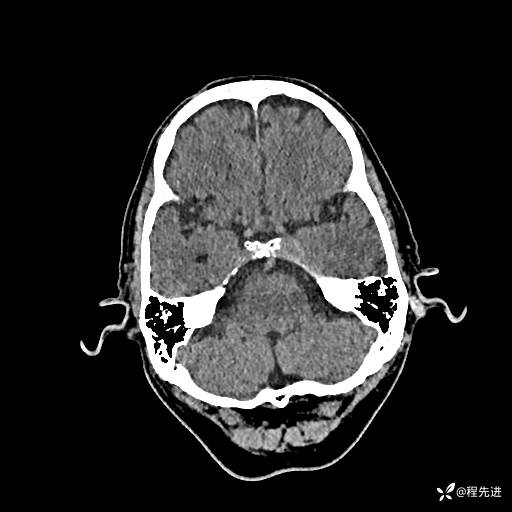

CT平扫: